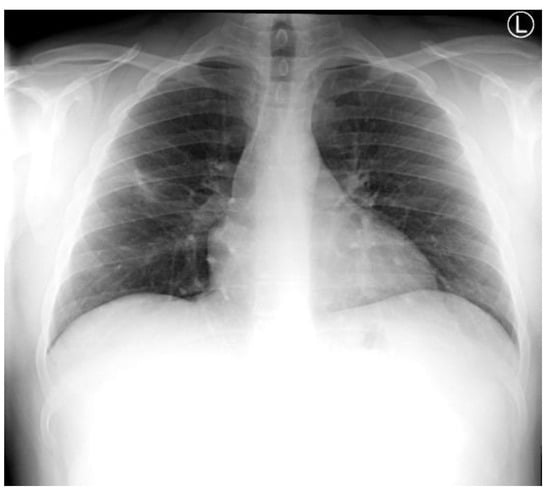

Chest X-ray showed a cavitating lesion in the right upper lobe (RUL), consistent with a cavitating pneumonia (Figure 1). He was empirically commenced on IV amoxicillin/clavulanate 1.2 g TDS and PO clarithromycin 500 mg BD for community-acquired pneumonia in accordance with local antibiotic guidelines.

Figure 1.

Admission chest X-ray demonstrating a right upper lobe cavitating pneumonia.